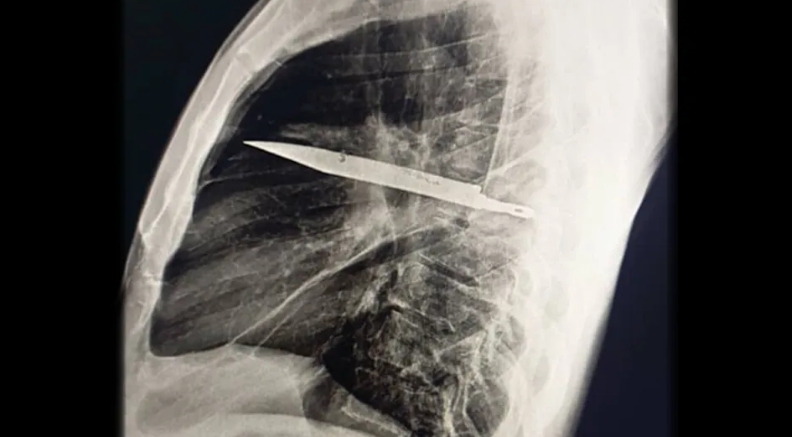

DAR ES SALAAM – Lekári v Tanzánii objavili u 44-ročného muža kuriózny a zároveň desivý prípad. Po tom, čo sa sťažoval na výtok hnisu z hrude, mu röntgen odhalil, že má v tele už osem rokov uviaznutú čepeľ noža. Zranenie pochádzalo z útoku, ktorý utrpel pred rokmi – a napriek tomu, že prežil bez väčších ťažkostí, kovová čepeľ v jeho hrudi ticho prečkala celé desaťročie.

Muž prišiel do nemocnice po tom, ako si všimol výtok hnisu pod prsnou bradavkou. Nemal však žiadne bolesti, horúčku ani dýchacie problémy, informuje na svojom webe Live Science. Lekári si najskôr všimli, že pravá časť jeho hrudníka sa pri dýchaní nepohybuje, a pri bližšom vyšetrení objavili otvorenú ranu. Počas rozhovoru pacient priznal, že približne pred ôsmimi rokmi bol napadnutý a viackrát bodnutý do hrude, chrbta a brucha. Vtedy mu rany len zašili, bez ďalších vyšetrení či röntgenových snímok.

Až súčasné vyšetrenie ukázalo šokujúci nález – čepeľ noža uviaznutú medzi rebrami a lopatkou. Kov sa dostal hlboko do hrudníka, no telo si okolo neho vytvorilo fibrózny obal, ktorý zabraňoval zápalu či bolesti. Práve preto muž necítil žiadne výrazné príznaky celé roky.

Chirurgovia následne pristúpili k zložitej operácii. Otvorili hrudník, odstránili zvyšok noža, vyčistili ranu, odviedli hnis a nasadili antibiotickú liečbu. Pacient sa po niekoľkých dňoch zotavil a po kontrolách o dva a šesť týždňov bol úplne v poriadku. Podľa odborníkov ide o mimoriadne zriedkavý prípad. Lekári pripomínajú, že pri akýchkoľvek bodných poraneniach je nevyhnutné urobiť zobrazovacie vyšetrenia, pretože cudzie predmety môžu v tele pretrvať celé roky bez zjavného prejavu – no s rizikom vážnych komplikácií.